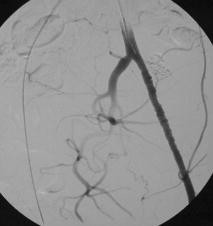

Abb. 2

Abb. 4